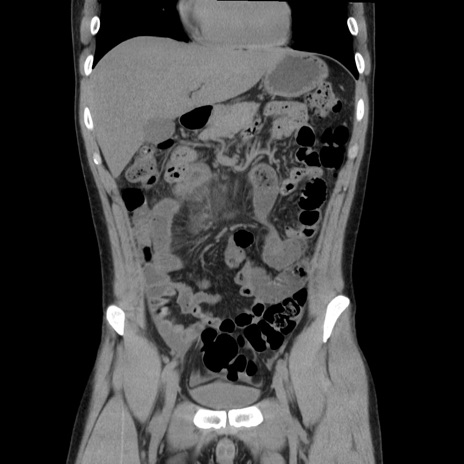

症例36(冠状断像)

【症例】20歳代 男性

【主訴】心窩部痛

【現病歴】今朝より上腹部痛あり。一旦軽快していたが再度出現したため救急要請。昨日夕に白身の魚を含む刺身を食べた。

【身体所見】BP 136/89mmHg、HR 74/min、BT 37.0℃、腹部:膨満、軟、心窩部に圧痛あり。反跳痛なし、筋性防御なし、腸雑音やや亢進あり。

【データ】WBC 17700、CRP 0.48